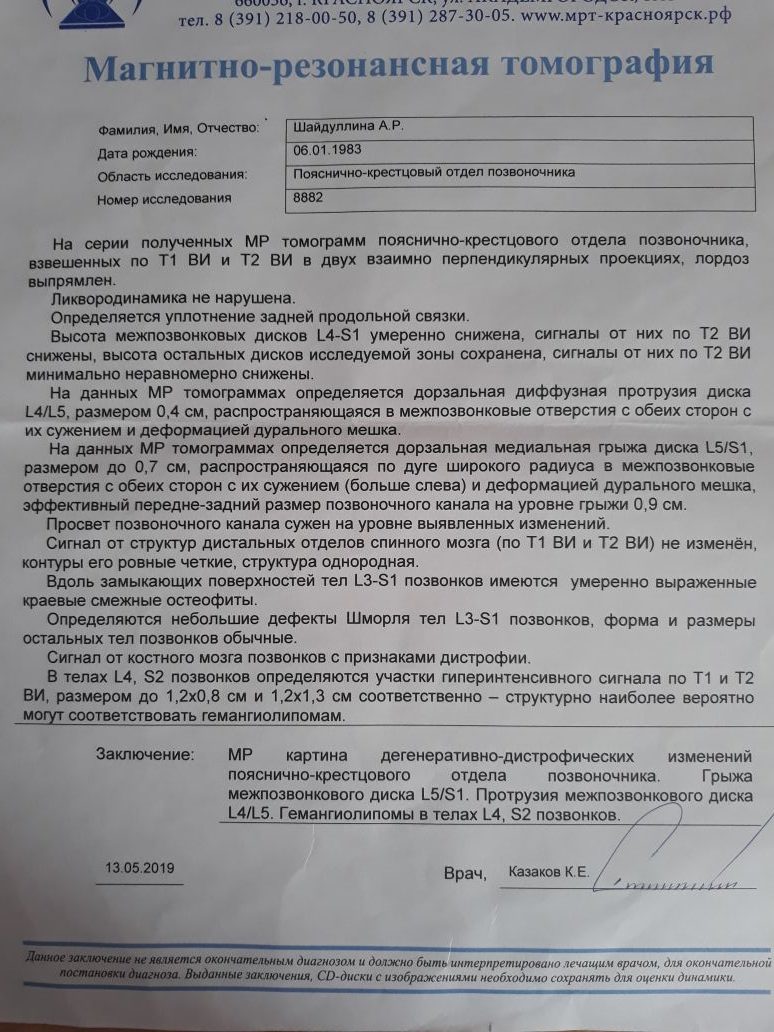

МРТ головного мозга: Расшифровка снимков и Интерпретация

Раздел: Визуальные уроки